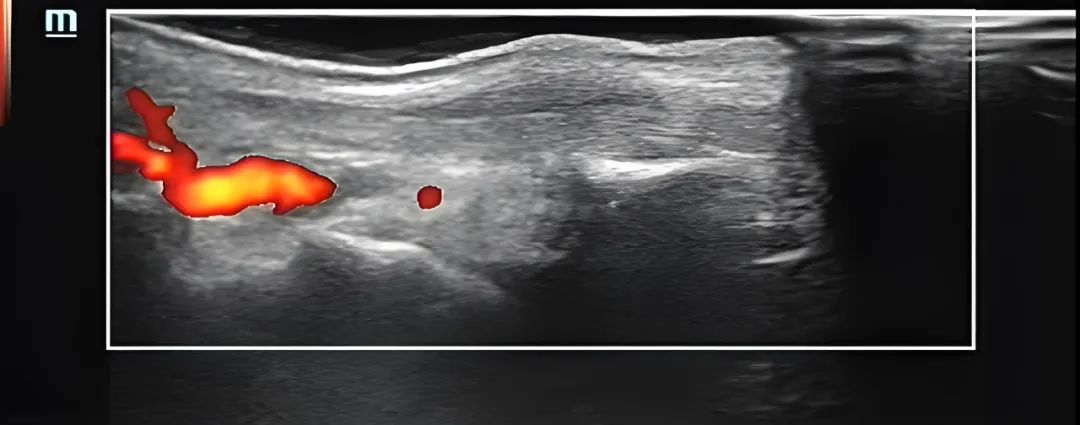

▲术后(腱鞘血流明显减少)